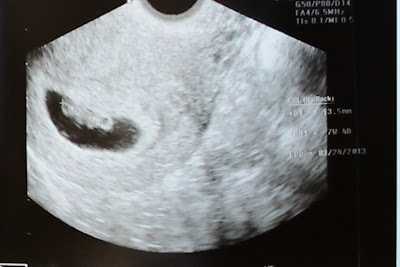

Our ultrasound was one I will never forget. And one like I've never seen in all my pregnancies.

"Beano" impressed us all with his amazing growth in the ten days since our last appointment.

*Measuring 13.5 mm

*7 weeks and 4 days (a day ahead)

*Sportin' little arm buds already

*With a healthy heartbeat

*An expected due date of March 24, 2013